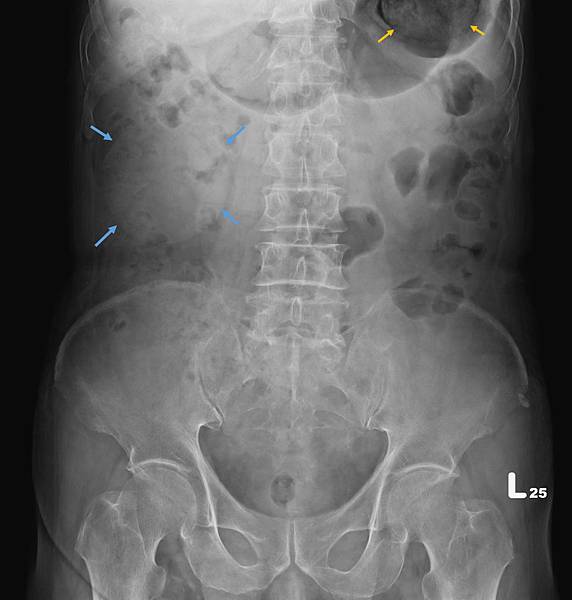

類似的病例很多,下面是上週門診時的胃酸逆流病例,KUB如下:

72歲女性,乙狀結腸(黃箭頭)充滿糞便,但她會告訴你,她每天都有解便。如上圖所示,這樣的病例,病人直腸(藍箭頭)糞便清得很乾淨。